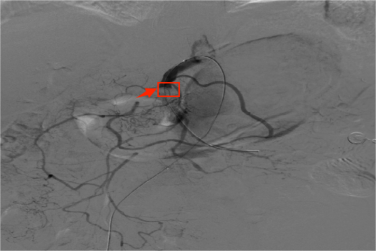

急性肠系膜上动脉栓塞可进一步出现肠管坏死、感染性休克甚至危及生命,而尽早正确诊断、及时治疗是降低病死率的关键。传统的治疗方法是内科的药物保守治疗和外科的切开取栓以及肠管切除,但存在效果不佳和创伤大、病死率高而增加治疗的难度。介入治疗的开展,很好的解决了这一难题。介入治疗存在创伤小、安全、副作用少等优势,对肠系膜上动脉栓塞的治疗达到了快速高效的治疗效果。普外科二区立即组织科内讨论,同时邀请胸心血管外科、重症医学科专家进行急会诊,完善术前准备及应急预案后,立即将患者送介入室行肠系膜上动脉造影术+肠系膜上动脉球囊扩张术+肠系膜上动脉置管术溶栓术。术后,患者腹痛明显缓解,肠鸣音正常,无腹膜炎征象,肛门排气、排便。